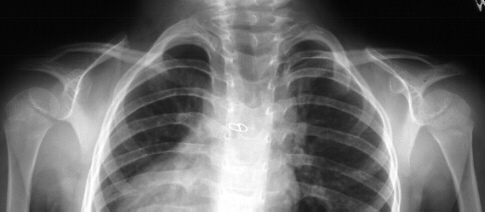

This is a 5 year and 3 month old white female was the product

of a full-term normal spontaneous vaginal delivery with a diagnosis

of CHARGE syndrome (defects of the eyes, ears, heart, choanal

atresia (primordal oronasal opening into the brain, mental retardation,

and genital hypoplasia). She presented for evaluation of a webbed

neck, left side worse than right. The child has developmental

delay and began walking at 4 years of age. She had undergone previous

surgery for strabismus and an atrial septal defect. Physical exam

revealed defects of the eyes and ears, the neck was shortened

and webbed (left worse than right). The back, shoulders and scapula

were elevated (left worse than right). The scapula was rotated

down and away from spine. Shoulder abduction was 110 degrees on

right and 100 degrees on left.